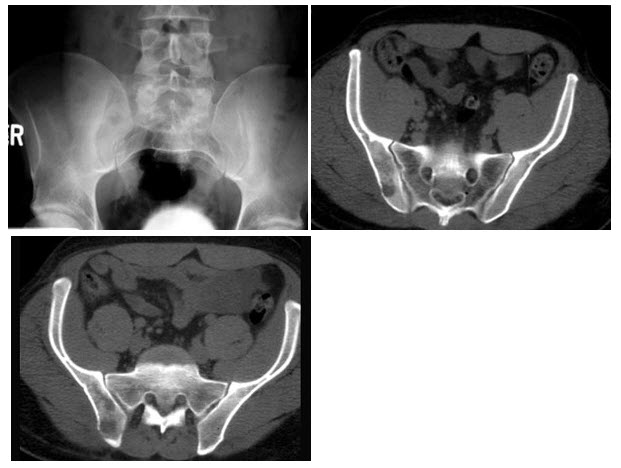

8、单项选择题

男,58岁,患者右季肋区疼痛,皮肤黄染,可触及肿大胆囊,B超提示胆囊颈部肿块影,CT所见如图,最可能的诊断是()

9、单项选择题

男,56岁,间歇性血尿半年余,根据所示图像,最可能的诊断是()

A.膀胱结石

B.膀胱血块

C.膀胱结核

D.膀胱癌

E.膀胱息肉

10、单项选择题 关于肾脏CT平扫表现,错误的是()

A.轴位图像上显示为圆形或椭圆形软组织密度结构

B.能够分辨肾皮、髓质

C.肾窦呈脂肪性低密度

D.肾盂呈水样低密度

E.肾门区肾动脉、肾静脉呈软组织密度窄带影

11、单项选择题

男,46岁,无痛性腹部肿块10月余,进行性增大伴消瘦2个月,结合图像,最可能的诊断是()

A.脂肪肉瘤

B.纤维肉瘤

C.神经源性肿瘤

D.滑膜肉瘤

E.转移瘤